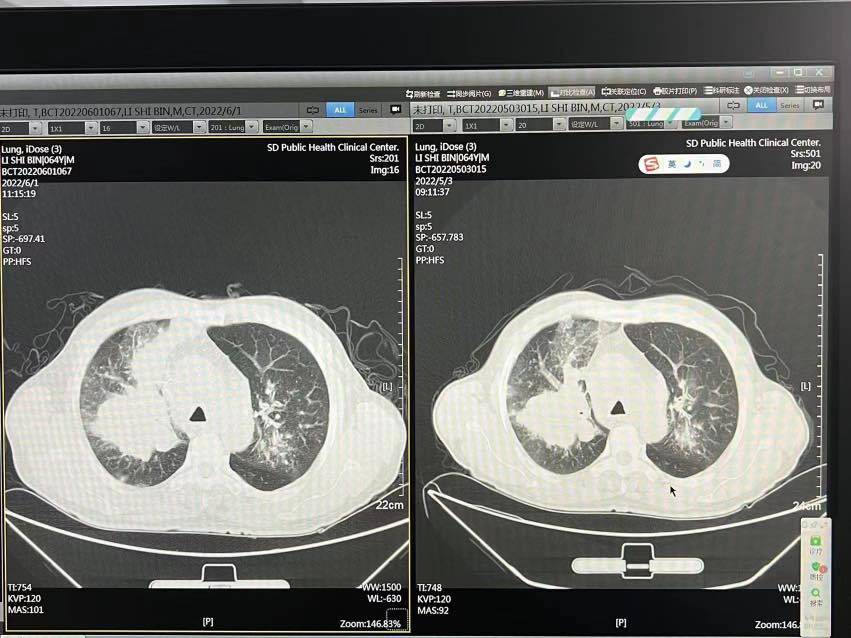

第一次化疗后在家总体体感还行,出院后也没有新发的不良反应。出院后几天又开始胸闷,担心了好久是不是出现了胸水,是不是无效,是不是假性增大等等。这次入院后拍了CT,肿瘤变化不大(没大也没小),一个多月不变也算是有效吧。胸闷原因也找到了,出现了阻塞性肺炎,估计是肿瘤压迫导致气道不通引起的吧,继续对症抗感染吧。

肿标CEA 仍是很高,但是有下降,从643降低到555。